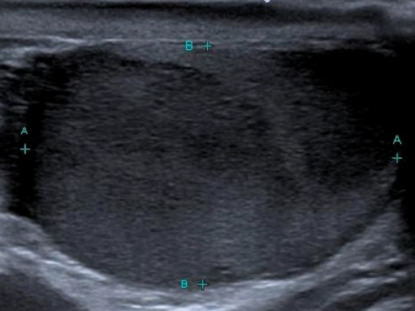

L’échographie révèle une masse hypoéchogène hétérogène du testicule droit (figure). Le TEP-scan montre également une fixation isolée au même niveau, sans atteinte ganglionnaire ni viscérale.